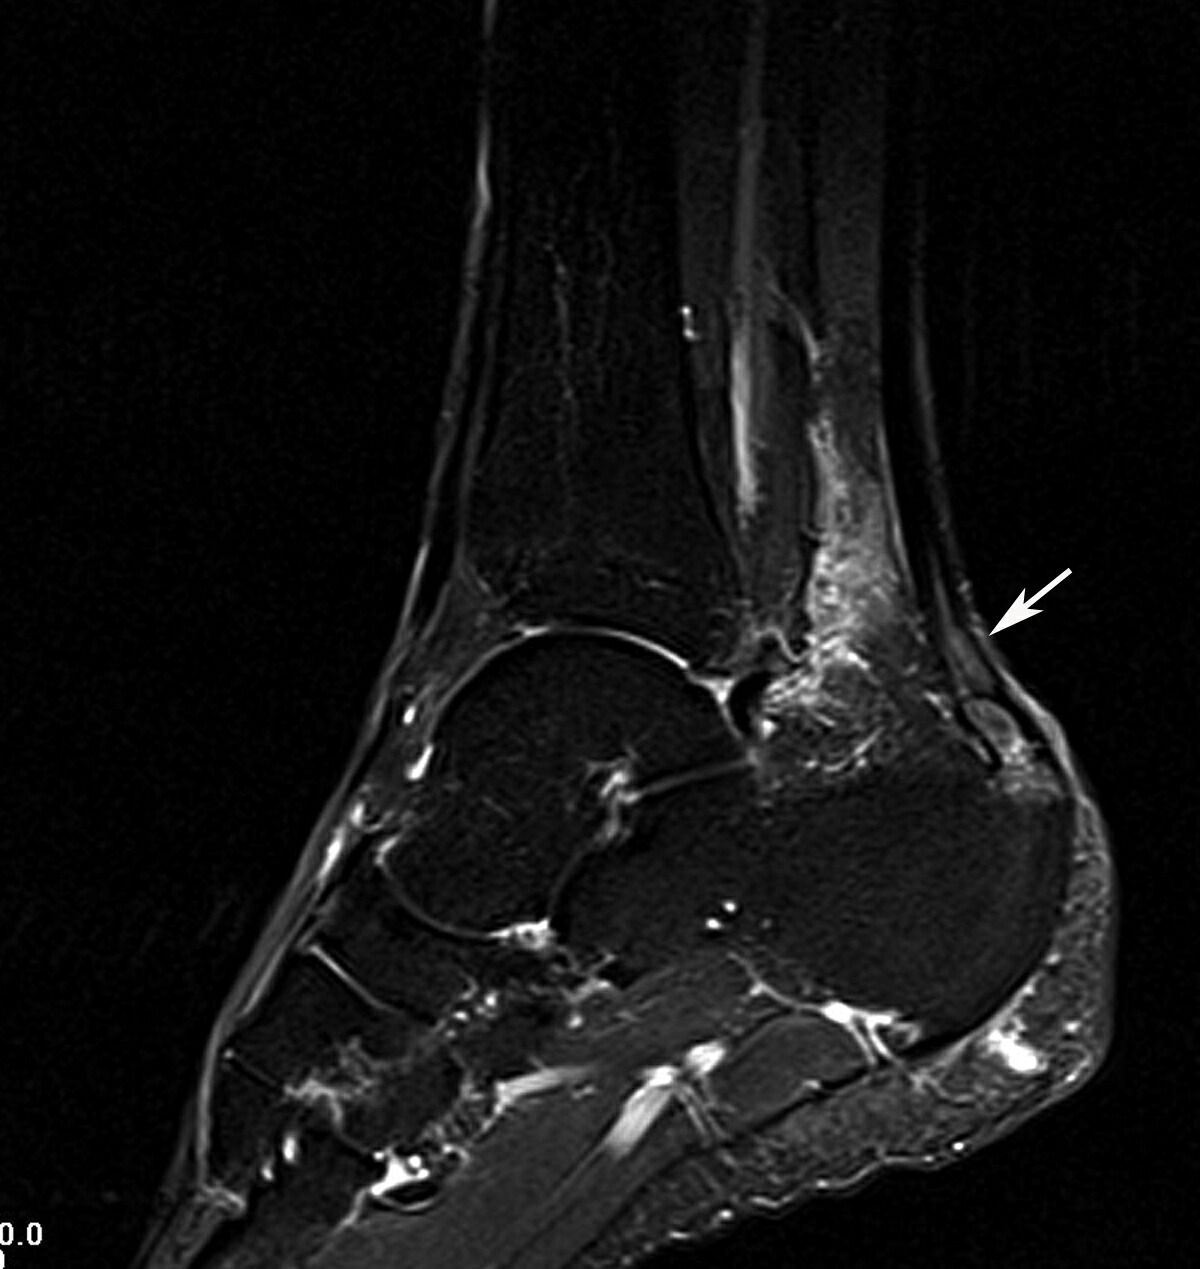

- Investigations: MRI, Ultrasound